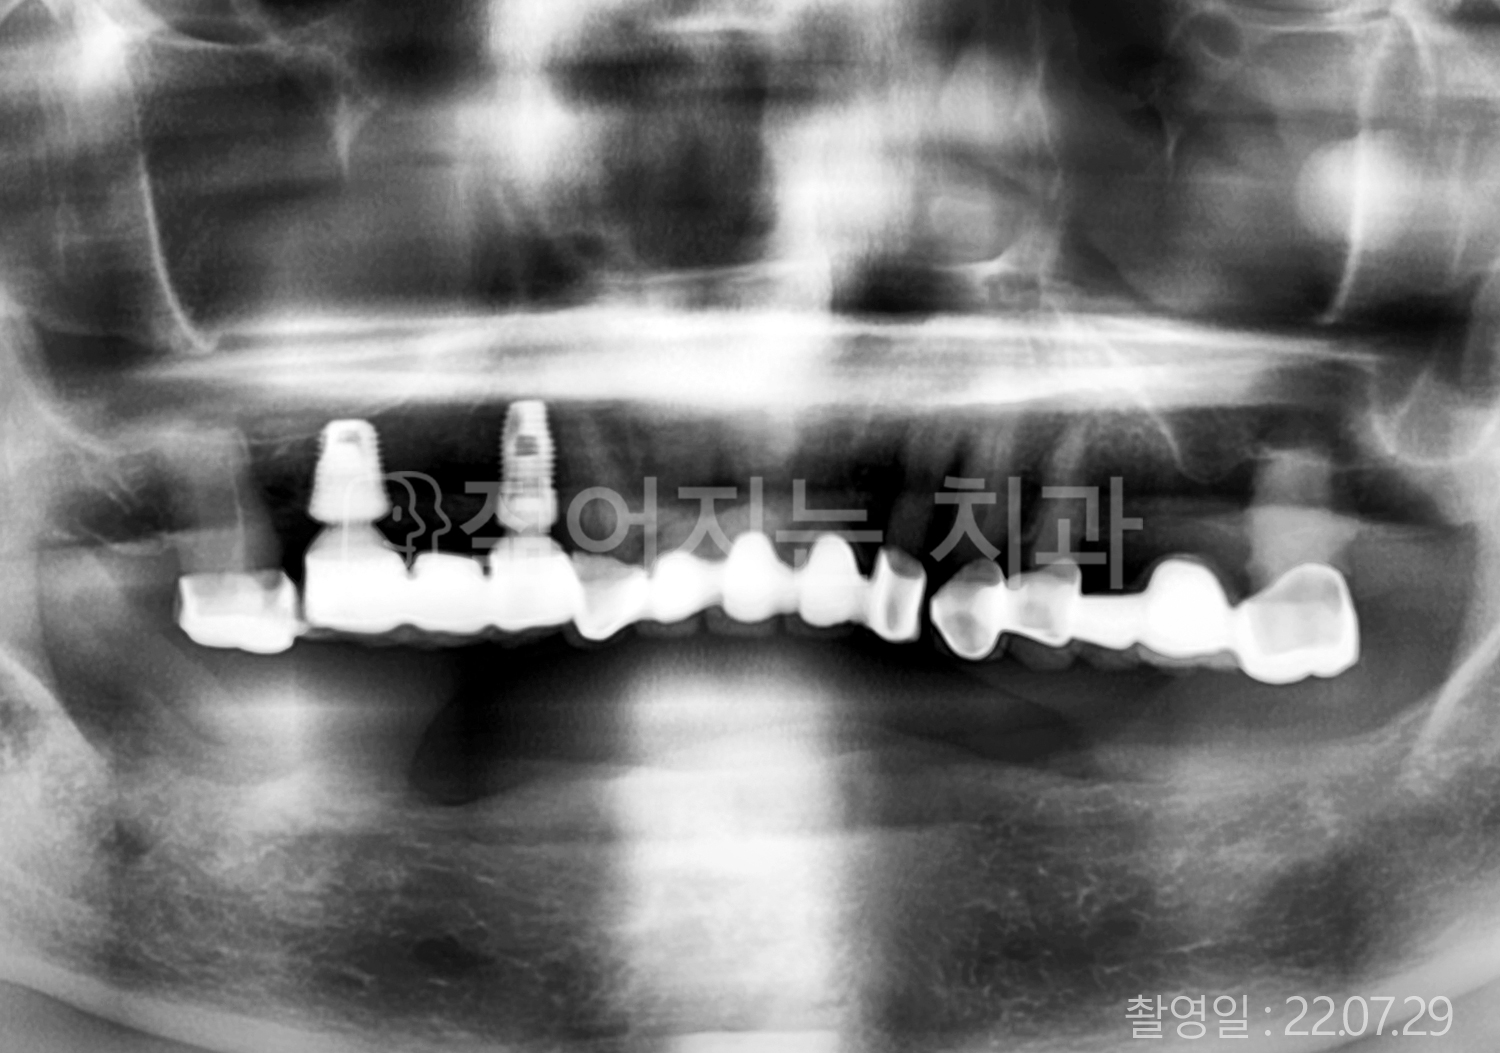

• 70대 고혈압, 고지혈증 전체치아 10개 이상 임플란트

• 60대 당뇨, 간염 전체치아 10개 이상 임플란트

• 70대 고혈압, 당뇨 전체치아 10개 이상 임플란트

• 60대 고혈압, 고지혈증 전체치아 10개 이상 임플란트

• 60대 전체치아 10개 이상 임플란트